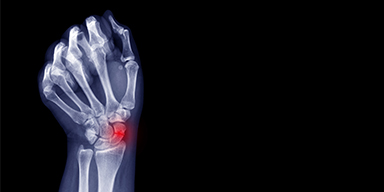

Les fractures fraîches du scaphoïde : comment en améliorer la prise en charge ?